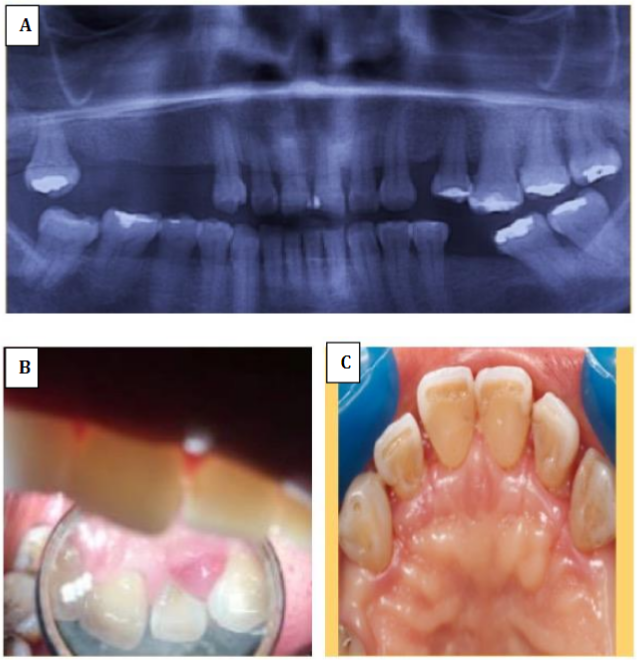

Paciente femenina de 52 años quien acude a consulta odontológica por presentar sangrado espontáneo e indoloro a nivel de encía de arcada superior, no reporta consumo de medicamentos o antecedentes médicos u odontológicos de importancia. Al examen clínico se observó encía eritematosa, de textura lisa y brillante, de consistencia blanda en arcada superior, presentó sangrado al sondaje (SS) en todos los órganos dentarios presentes en dicha arcada y en algunos de la arcada inferior, se encontró bolsa periodontal (BP) a nivel de dos órganos dentarios en arcada superior y de dos órganos dentarios en arcada inferior, de igual forma se evidenció presencia de cálculos (C) en múltiples órganos dentarios de ambas arcadas dentarias, exposición de furca y sensibilidad al frío en órganos dentarios número 26 y 27. Al examen radiográfico se observa pérdida ósea vertical moderada en órganos dentarios número 18, 13, 12 y 25, pérdida ósea horizontal moderada en órganos dentarios número 26 y 27 y ausencia de órganos dentarios 14,15, 16, 17, 24, 36 y 46 (Figura 1A).

Figura 1.

(A) Radiografía panorámica. Se observa pérdida ósea vertical moderada en órganos dentarios 18, 13, 12 y 25, pérdida ósea horizontal moderada en órganos dentarios 26 y 27. (B) Vista clínica de papila interdental en órganos dentarios 22 y 23. (C) Vista clínica postoperatoria en sector anterosuperior.

El tratamiento que se realizó en este caso, inicialmente fue una fase higiénica el 17-04-2018 (Tabla 1), que se basó en un raspado y alisado radicular (RAR) a campo cerrado en arcada superior, con anestesia tópica en Chispray, a los dos días la paciente presentó lesiones inflamatorias, asintomáticas a nivel de órganos dentarios 22-23-27 (Figura 1B). Para llegar al diagnóstico de absceso periodontal se tuvo en cuenta la presencia de bolsas periodontales preexistentes a nivel de los órganos dentarios afectados en conjunto con los signos clínicos como inflamación, y se descartó el diagnóstico de absceso AP gingival debido a que por lo general esta se encuentra en sitios no asociados con enfermedad periodontal, por lo cual no se presenta bolsa y usualmente se encuentra limitado a encía marginal10. Como tratamiento el día 24-04-2018 se realizó RAR a campo abierto con detoxificación con tetraciclina en órganos dentarios 22-23-25-26-27. Se formuló, amoxicilina cápsulas 500 mg, una cada 8 horas durante 7 días, ibuprofeno tabletas 600, mg una cada 6 horas, por dolor. Se hizo control postoperatorio ocho días después, donde no se observó ninguna alteración intraoral (Figura 1C). A los 15 días siguientes, se realizó extracción de órganos dentarios 26-27, debido a que después del tratamiento los dientes presentaban extrusión, sensibilidad y movilidad avanzada, los cuales fueron tratados, pero no hubo evolución. Además, el pronóstico restaurador era desfavorable para estos dientes.